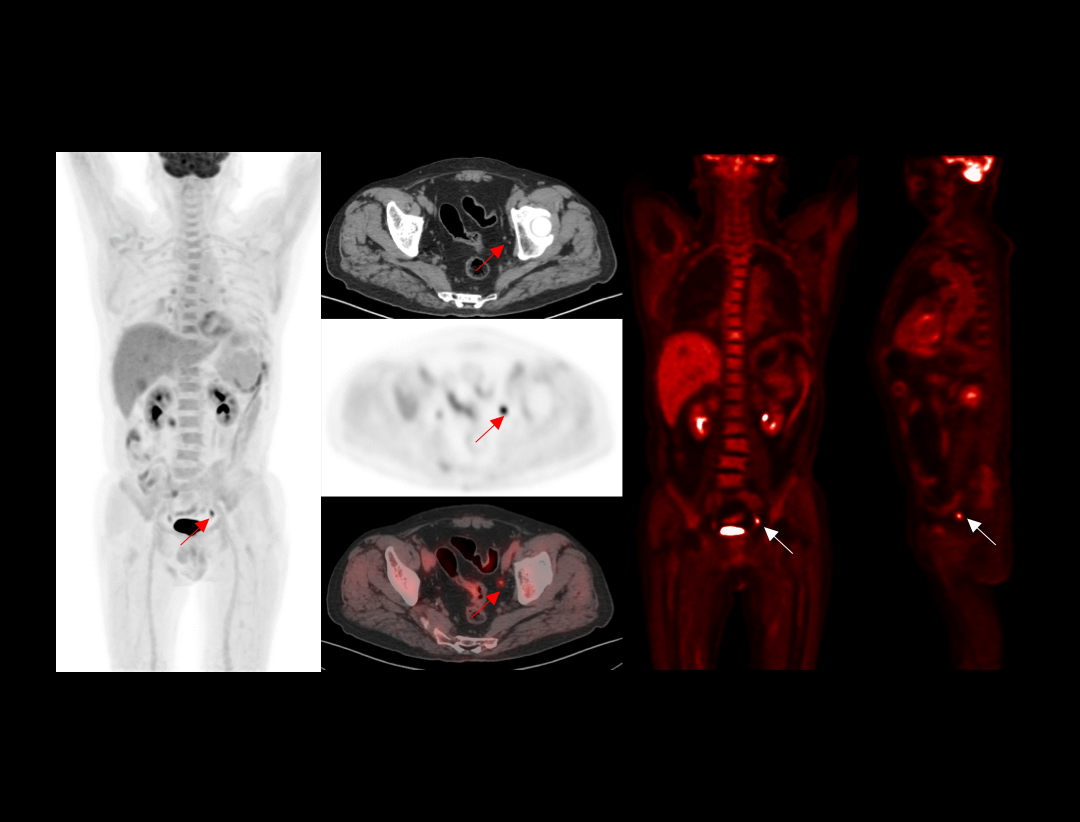

With the unique Integrated-Light-Guide Digital PET technology and a 160-slice CT system, uMI Vista combines high quality functional images with fine anatomical structure visualization. The state-of-the-art reconstruction technology and comprehensive applications further boost diagnostic precision in oncology, neurology and cardiology.

Clarity Imaging Chain

2.9mm NEMA Resolution

Outstanding resolution performance is achieved through systematic imaging chain engineering.

HYPER Iterative Reconstruction

Improves signal-to-noise ratio and contrast recovery to aid lesion detectability and quantitative accuracy.